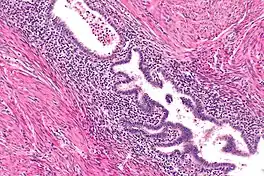

Histopathology of uterine adenomyosis. H&E stain.

The most common diagnostic imaging modalities for uterine adenomyosis include transvaginal ultrasonography (TVS) and magnetic resonance imaging (MRI). Though surgical excision and microscopic examination of the tumor allow for a definitive diagnosis, these imaging studies offer a non-invasive approach and have a sufficient resolution for a diagnosis.[2]

Diagnosis with transvaginal ultrasonography can potentially be challenging due to the similar appearance of uterine leiomyomas (also known as uterine fibroids). Careful evaluation of the margins of the mass, the vascular flow patterns through the tumor, and the degree to which the tumor distorts the uterus may aid in differentiating these masses with ultrasound.[2] MRI is highly effective at distinguishing between uterine adenomyomas and leiomyomas.[3]